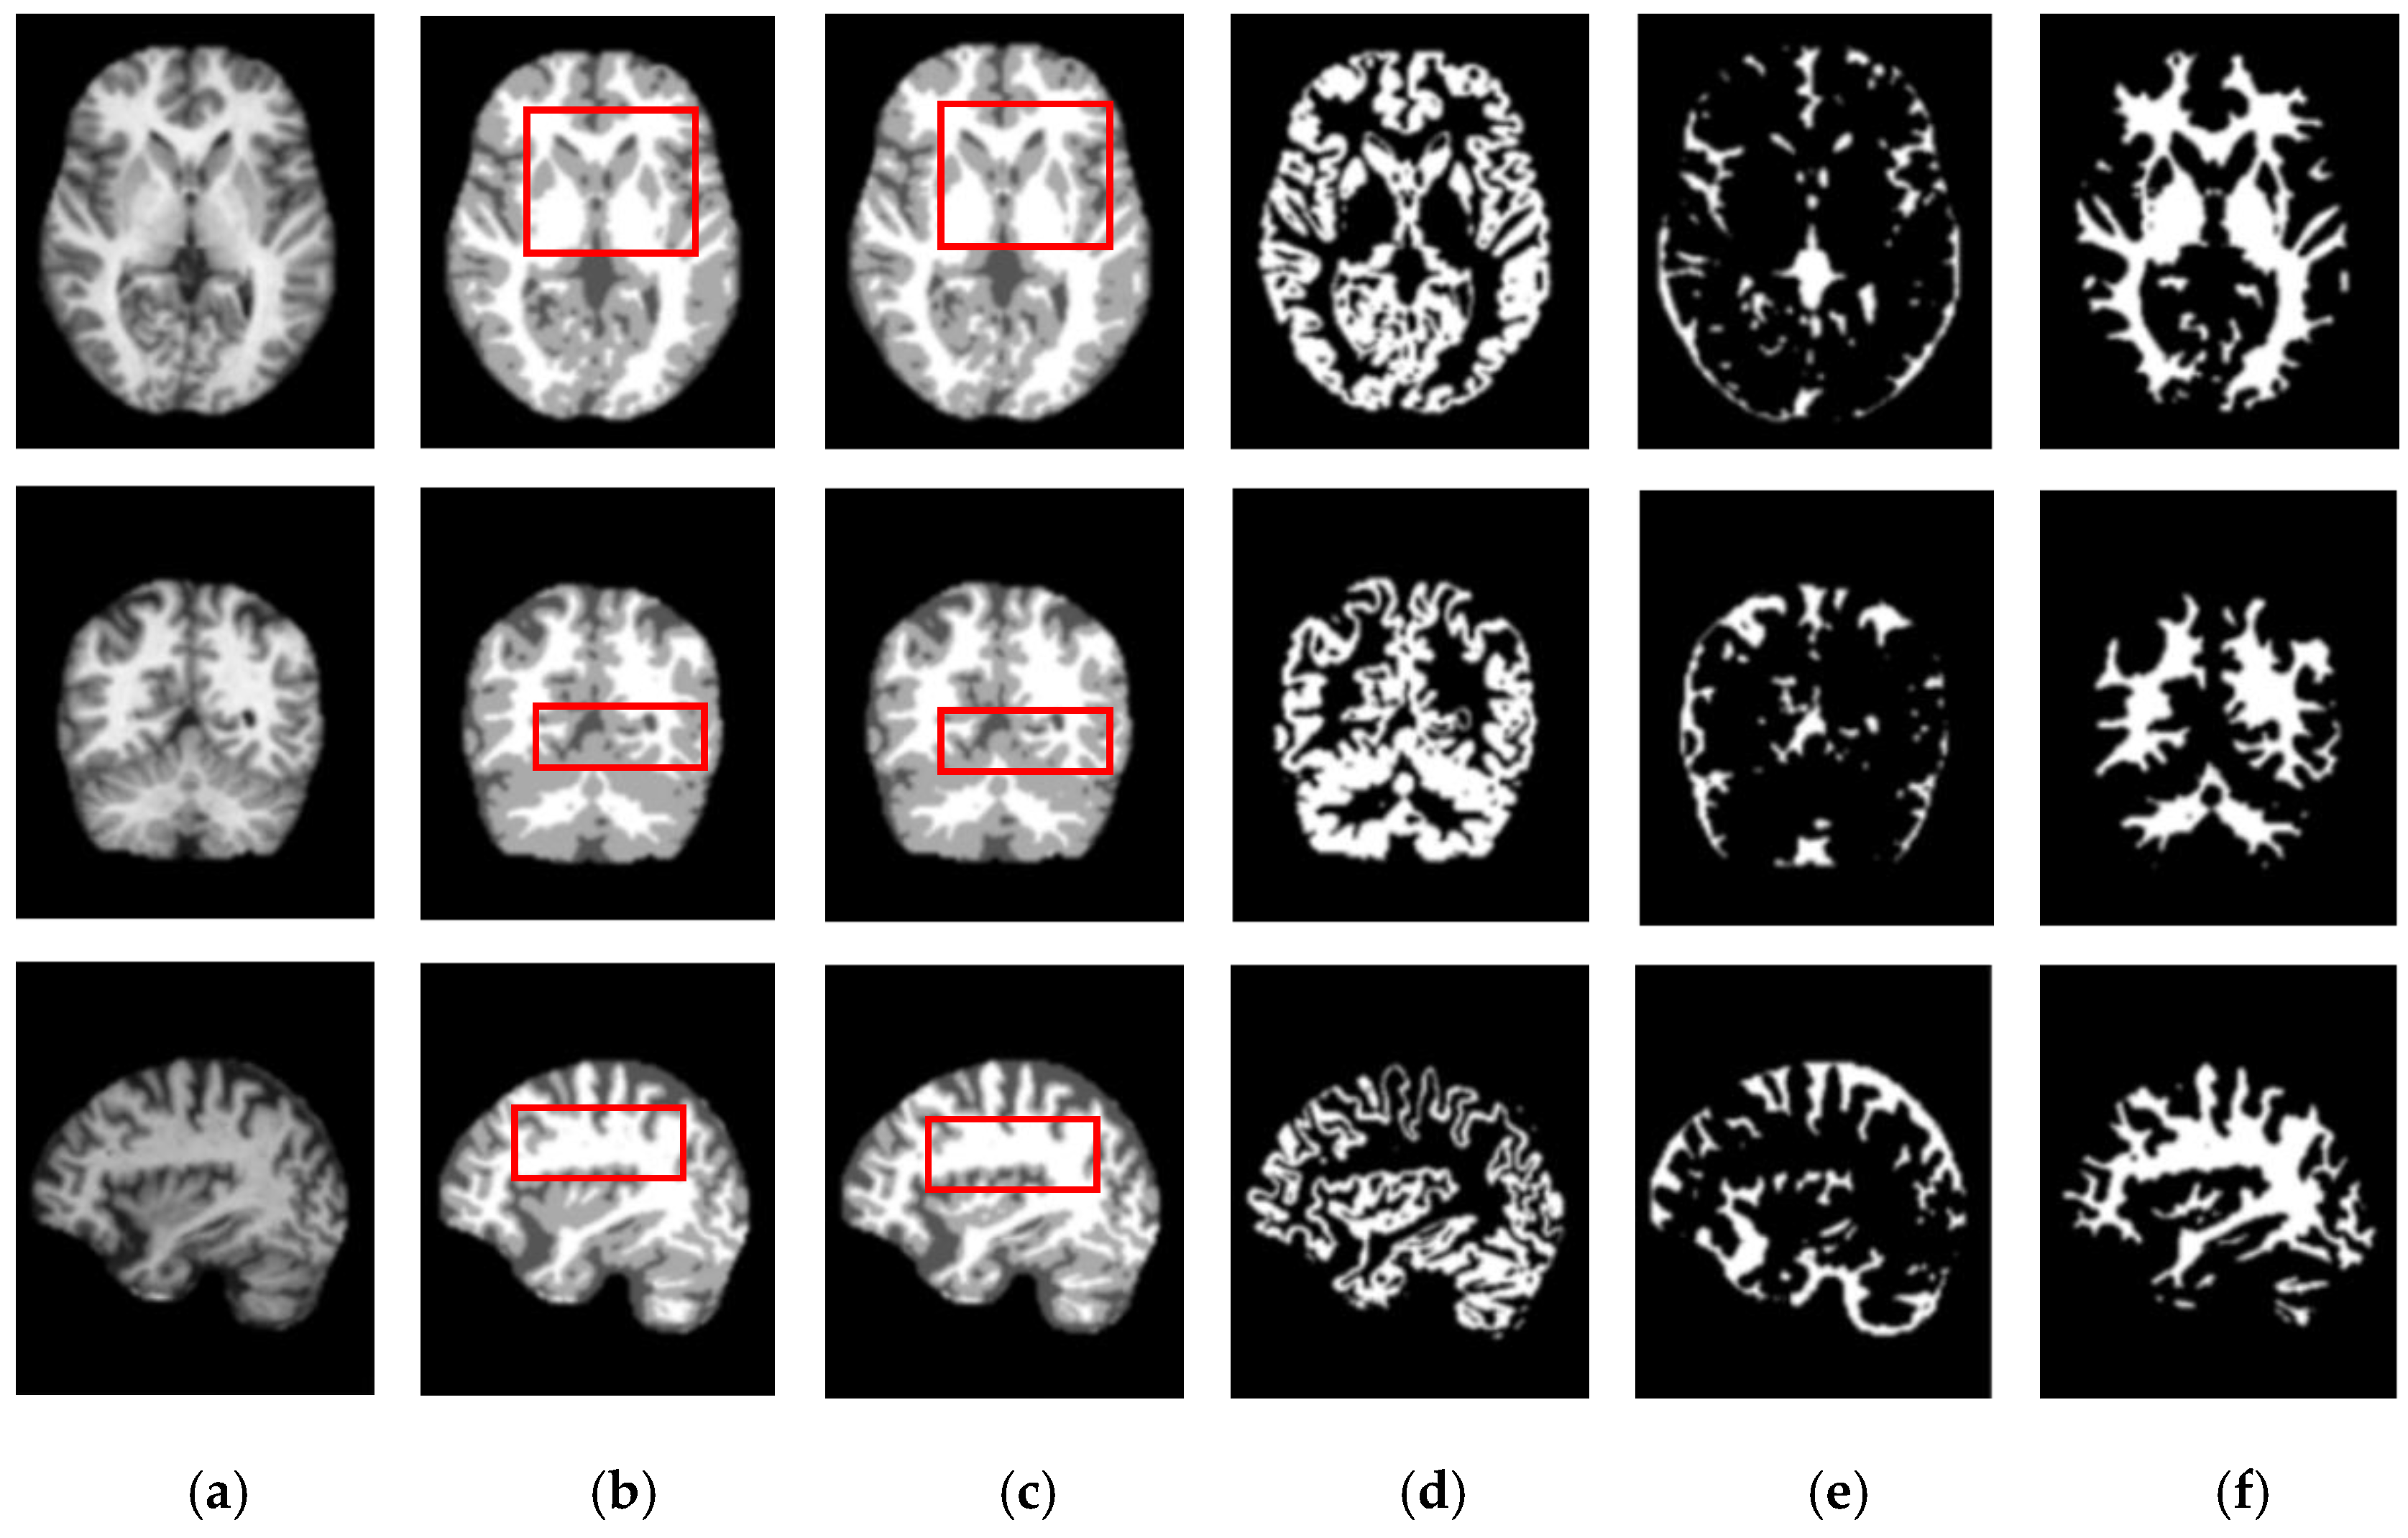

Figure 5 and Figure 6 show the segmentation results for the axial, coronal, and sagittal planes of the OASIS and IBSR datasets, respectively. The figures show that the proposed approach achieves well-segmented performances for GM, WM, and CSF of the brain MRI on both datasets. The axial plane shows the most informative details in the central slices of the MRI compared to the other planes. Thus, the segmentation results for the axial planes show the segmentation performance most effectively. In addition, the highlighted boxes in Figure 5 and Figure 6 show that the quality of sagittal and coronal images is highly promising without any difference in every detail. From the results of Figure 5 and Figure 6, it can be inferred that the proposed method can extract complicated pattern features from all three planes.

Figure 5.

Segmentation results for the axial, coronal, and sagittal planes of the brain MRI image (top to bottom) on the OASIS dataset using the proposed method. (a) Original input images, (b) ground truth segmentation map, (c) their predicted segmentation map obtained by using the proposed method, (d) predicted GM (binary map), (e) predicted CSF (binary map), (f) predicted WM (binary map).